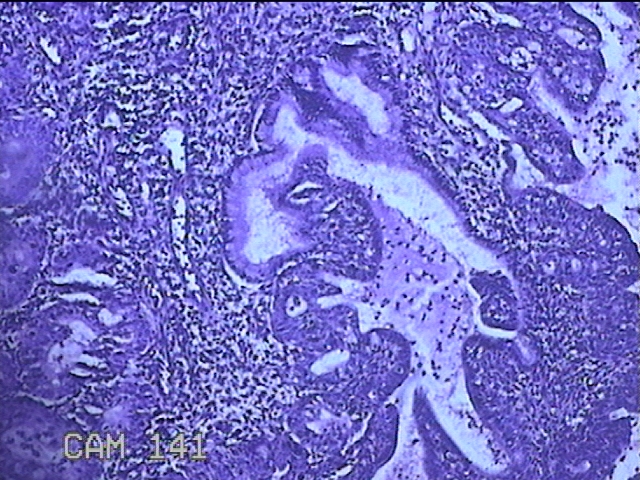

宫颈赘生物

性别

女

年龄

36岁

临床诊断

一般病史

发现宫颈赘生物1个月。

标本名称

大体所见

灰白暗红色肿物1x0.7x0.2cm一个,表面糜烂。

图3